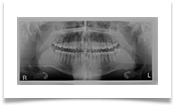

Nel nostro Studio impieghiamo un sistema radiografico computerizzato, il Vista Scan Plus della Dürr che consente di ottenere immagini di alta qualità (vedi confronto analogico/digitale) con dosi radiogene sensibilmente più basse per il paziente.

Con Vistascan Plus siamo in grado di ottenere, nel giro di pochi minuti, tutte le immagini che ci servono per un corretto ausilio diagnostico: bitewing, endorali, ortopantomografie, teleradiografie.